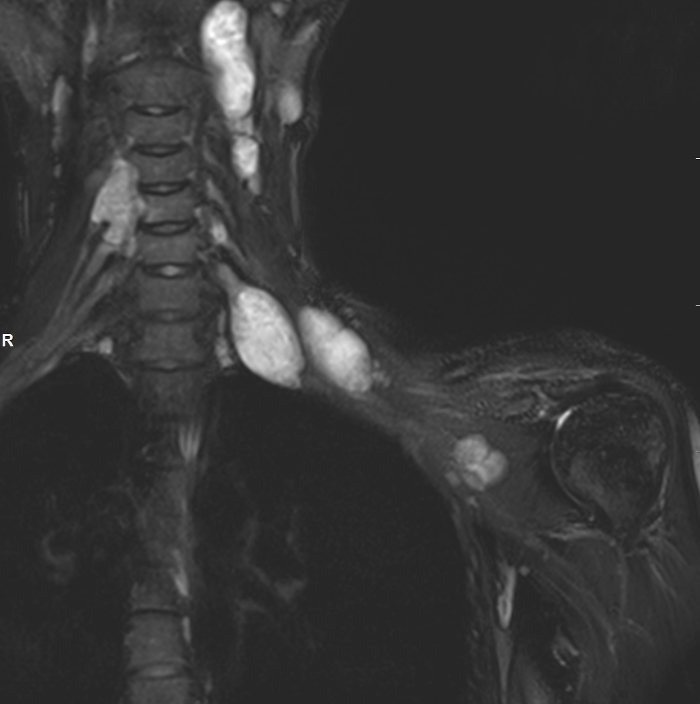

Neurofibroma brachial plexus

Target sign

- hypointense centrally

- hyperintense peripherally